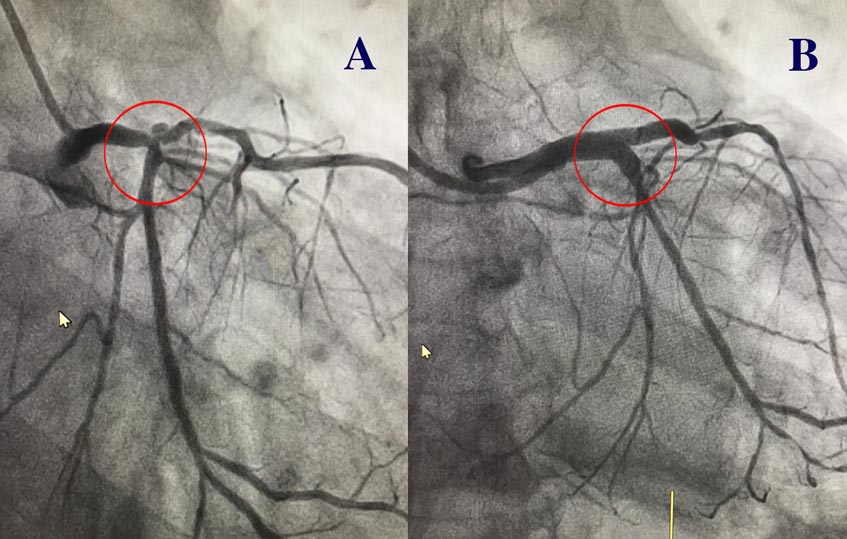

“Đây là vị trí ‘hiểm hóc’ thách thức cả ekip can thiệp đặt stent, khi phải ‘phá tảng băng’ để đặt cùng lúc 2 stent khai thông chỗ hẹp của hai nhánh động mạch”, bác sĩ Long nhấn mạnh.

Là một người trực tiếp thực hiện ca can thiệp, ThS.BS Võ Anh Minh, Trưởng đơn vị Can thiệp mạch vành, Trung tâm Can thiệp mạch sử dụng kỹ thuật kissing-stent để giải quyết bài toán khó này. Đầu tiên, một đoạn stent được đưa vào động mạch vành bị hẹp tại vị trí thân chung, sau đó thực hiện nong bóng để stent nở ra đúng kích thước dự tính nhằm lưu thông máu tốt nhất. Sau khi đặt thành công đoạn stent thứ nhất, bác sĩ tiếp tục đưa đoạn stent thứ hai vào nhánh mạch máu cạnh bên, tạo thành một vị trí vuông góc (2 stent tạo thành hình chữ T).

Bởi vì cả 2 nhánh động mạch liền kề nhau đều bị hẹp, đòi hỏi phải áp dụng kỹ thuật can thiệp khó gấp nhiều lần so với đặt stent một nhánh động mạch. Do vậy trong suốt quá trình can thiệp, mọi thao tác của bác sĩ đều phải nhanh, chính xác, cẩn trọng và chỉn chu. Sau can thiệp, bệnh nhân hồi phục sức khỏe nhanh chóng, có thể đi lại, ăn uống bình thường và được xuất viện sau 2 ngày.